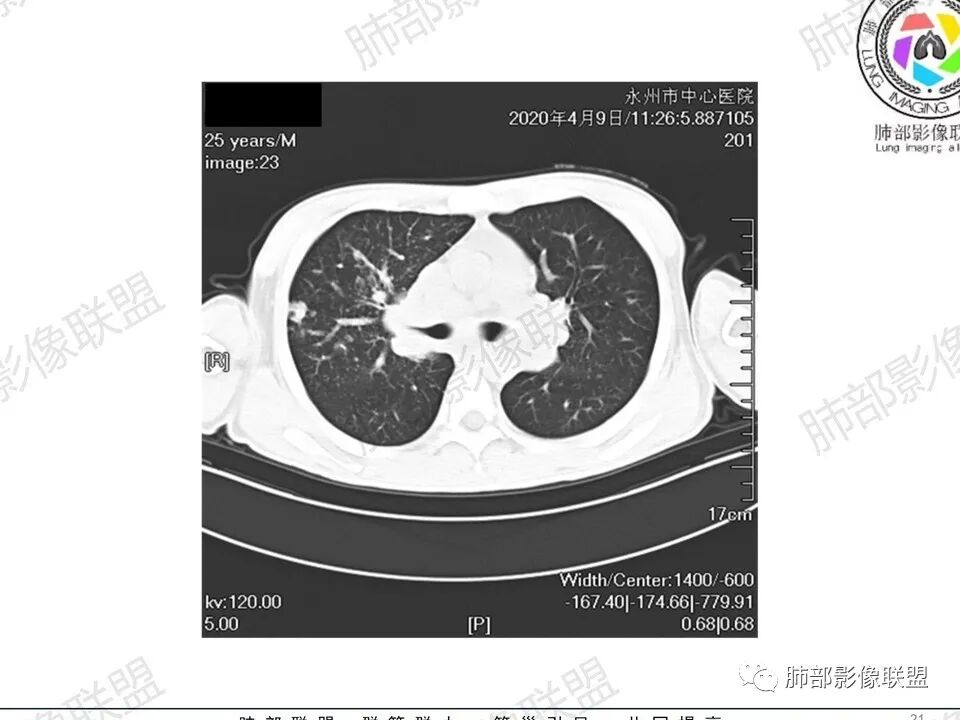

那个人:青年男性,慢性病程,咳嗽气促,伴盗汗胸痛。实验室,贫血,血沉快,C反应蛋白升高,低蛋白血症。影像,双肺散在斑片影,结节影,伴树芽,斑片影源支气管血管束分布,支气管走形自然,结节影有小空洞,有些周围有磨玻璃成分,小结节有些成串珠样改变,纵隔肺门淋巴结肿大,心腔低密度。考虑淋巴增值类疾病,结核?淋巴瘤?结节病?鉴别血管炎,实验室,影像不太支持

一切∮随缘:双肺多发大小不等结节,结节密度高,边缘清楚,部分结节内可见血管穿行,另右肺长条状实变影,内部可见支气管充气征,局部支气管壁增厚,双肺多发小树丫,双肺门及纵隔淋巴结肿大,部分融合,无增强,对淋巴结坏死无法判断,临床:年轻男性慢性病史急性加重,血象、CRP、ESR高,考虑一元论:结核(年龄加影像都符合),二元论:结节病或淋巴瘤+结核(建议CT增强及淋巴结穿刺),无原发肿瘤病史,癌性淋巴管炎代排。

Coke with ice :25岁。支气管血管束分布为主,同时有淋巴管型分布的小叶中心型结节。周围间质微小结节。中央带明显,右侧明显,中上肺明显。中央带向周围放射状分布。有空气潴留,支气管充气征,病变周围少于磨玻璃。双肺门纵膈多大淋巴结肿大。常规疾病谱:结节病,结核,荚膜组织包浆菌,淋巴瘤,还有卡波西肉瘤。诊断:结节病第一位,淋巴瘤第二位。查艾滋病,卡波西肉瘤第三位。

3、影像表现:双肺散在斑片影及结节影,部分结节内可见血管穿行,斑片影沿支气管血管束分布,近胸膜侧病变收缩不明显。部分中央淋巴间质增厚,小叶间隔增厚。病灶内支气管穿行,部分支气管略扩张。局部小结节呈串珠样改变。纵隔、肺门区、锁骨上及腋窝淋淋巴结肿大,部分有融合。心腔低密度。脾大。

2.双肺多发片影及结节影,边界可分辨,右肺中上叶较为密集,没有胸膜下分布优势。病灶实性密度为主,未见钙化及液化。

3.右肺较多微小结节,密度较为浅淡,部分沿血管束分布,未见沿小叶间隔及叶间裂分布结节影,未见典型的终末气道树芽。

淋巴瘤肺部浸润表现多样,多发结节影是其最常出现的影像学改变,尤其是霍奇金病。

2.右肺多发微小结节影,部分沿血管束分布,尽管未见小叶间隔改变,但双肺门淋巴结增大确实应当首先排除结节病,但经验上说,结节病的增大淋巴结密度往往较高、较密实,边界往往清楚,“独立性”很强,绝无“融合之嫌”!此外,较少出现贫血、脾大,临床表现也往往较轻微。

3.双肺多发结节影,没有明显的新旧不等,没有钙化,微小结节影密度偏低,边缘不够僵硬锐利;病灶区域穿行支气管显示良好,未见壁增厚及管腔狭窄,加之病灶如此广泛,病灶未见收缩、肺叶体积未见缩小,结核中毒症状不明显等等都不支持结核。